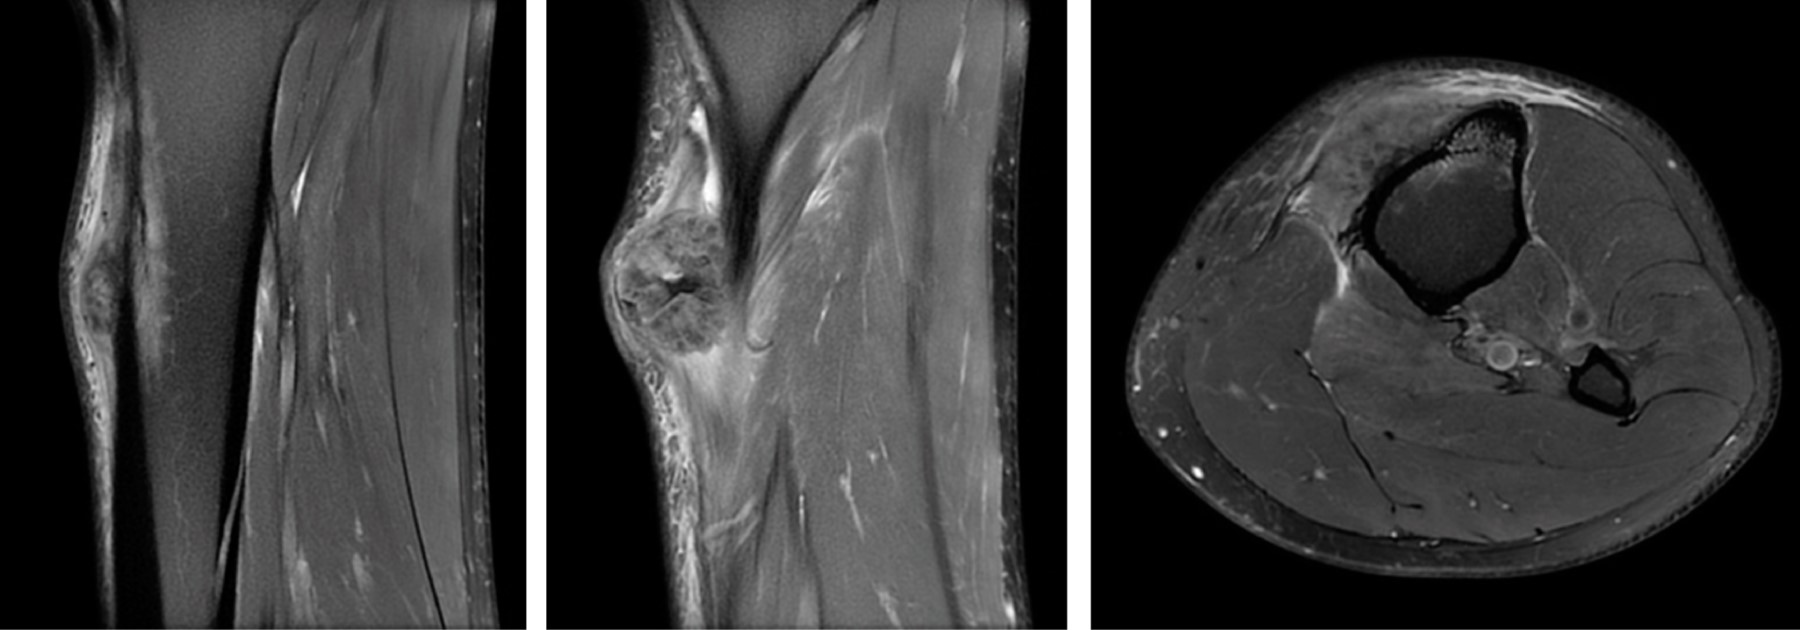

Initially a XR, CT and MR were performed showing a soft tissue tumor on the proximal aspect of the left tibia just inferior to the tibial tuberosity, size of 40 × 29 × 19 mm (coronal × sagittal × axial). Emerging from the anterior tibia periosteum and growing towards the subcutaneous tissue, hyperintense in T2 and hypointense in T1. Tumor presents with irregular and extensive internal calcifications (Figure 2). An initial biopsy was performed that was inconclusive, so an ultrasound guided biopsy was done afterwards with a 14G needle. The pathologist could not conclude between, hypertrophic fracture callus, osteoblastoma or osteosarcoma subtype osteoblastoma.

Three months later MR was repeated showing increase in size 42 × 40 × 27 mm and small areas of necrosis. Large attachment to the anterior periosteum remains with exophytic growth contacting the skin (Figure 3). With new imaging a third biopsy was performed guided with ultrasound. It showed trabecular osteoid areas that converge and areas of spindle cells with moderate cellular atypia, that suggested cPOS or HGSO.